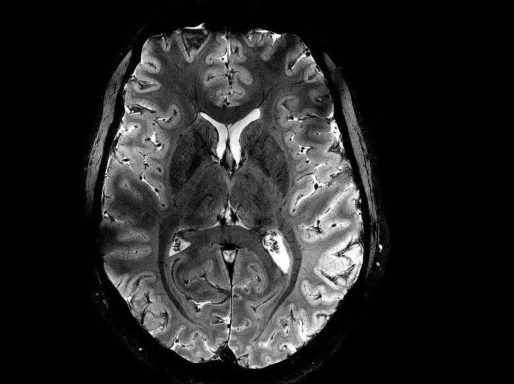

Bron NRC | Zó gedetailleerd zag de wereld de hersenen nooit eerder op een MRI-scan. Franse wetenschappers toonden de afgelopen week de scherpste afbeeldingen van de hersenen ooit, gemaakt met de allerkrachtigste MRI-scanner ter wereld. Die Iseult MRI-machine heeft een magnetische veldsterkte van 11,7 tesla.

De beelden die de nieuwe Franse superscanner kan maken van weefsels en structuren in het lichaam hebben een resolutie van 0,2 millimeter, in digitale ‘plakjes’ van 1 millimeter. In hersenweefsel komt dat overeen met een paar duizend neuronen. De gedetailleerde beelden werden gemaakt in ongeveer vier minuten. Reguliere scanners zouden er uren over doen om dezelfde resolutie te bereiken. Zo lang kunnen proefpersonen of patiënten niet stilliggen.

Op de gepresenteerde scans zijn zenuwbanen, bloedvaatjes en de verschillende lagen van de sterk geplooide hersenschors haarscherp zichtbaar. De Fransen durfden de proef met twintig vrijwilligers aan na inventariserende studies in 2021 op een pompoen.